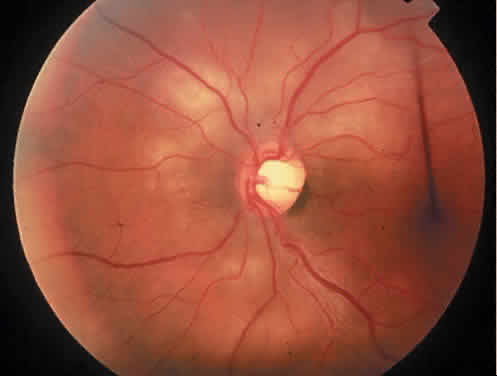

Protein S is a nonenzymatic cofactor necessary for the anticoagulant activity of activated protein C. Protein S by itself also has anticoagulant activity by forming a complex with C4b binding protein, a regulatory protein of the complement system. Protein S deficiency is inherited as an autosomal-dominant trait. Unlike protein C deficiency or antithrombin III deficiency, heterozygous protein S deficiency is not as strong a risk factor for thrombosis. Retinal artery occlusion has been described with protein S deficiency.25,29 Figure 2 shows a pregnant woman with protein S deficiency and a branch retinal artery occlusion (see Fig. 2).

Fig. 2. A 32-year-old woman during her third trimester of pregnancy with a branch retinal artery occlusion. She was found to have protein S deficiency.